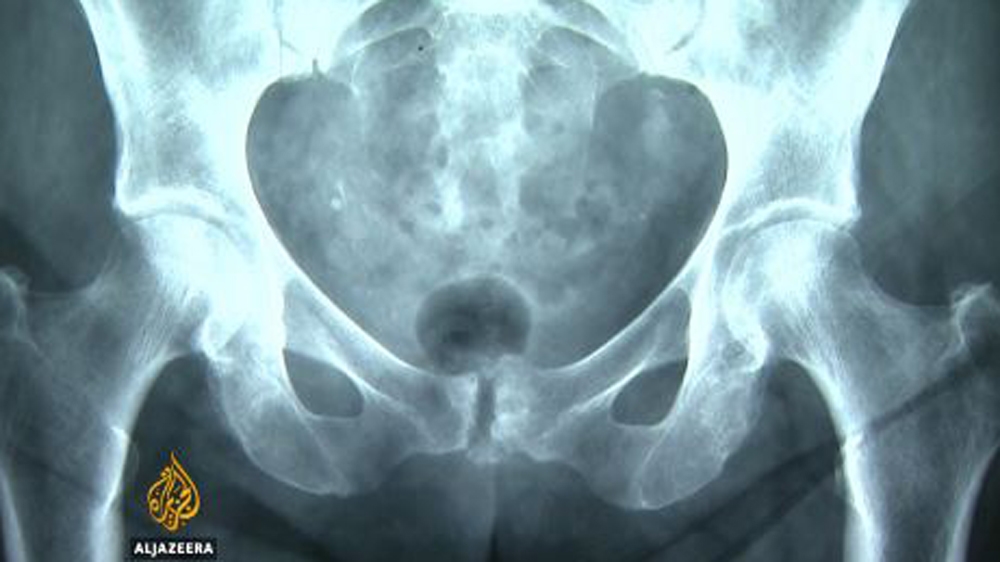

The procedure is called symphysiotomy: The symphys part refers to the pelvis, the “otomy” meaning separation.

Sawing open a woman’s pelvic bone to release a baby in the wrong position isn’t something any doctor would do on purpose.

The side effects, the catastrophic impact of breaking the pelvis, the purpose of which is to hold a body in place, were apparently ignored.